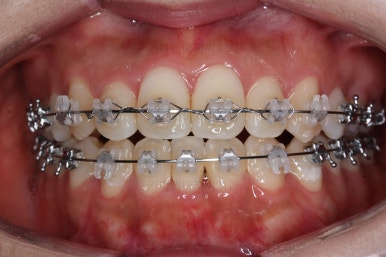

부분적으로 장치 셋팅을 다시 해줬고요.

밀고 당기기를 위해서 미니스크류를 셋팅했고요.

교합과 중앙선 및 디테일을 맞춰 나갑니다.

부산재교정 이니만큼 원하는 부분을 최대한 수용하여 개선하고 마무리를 합니다.

중앙선, 교합, 앞니 맞물림 등 모든 것이 좋아졌네요.